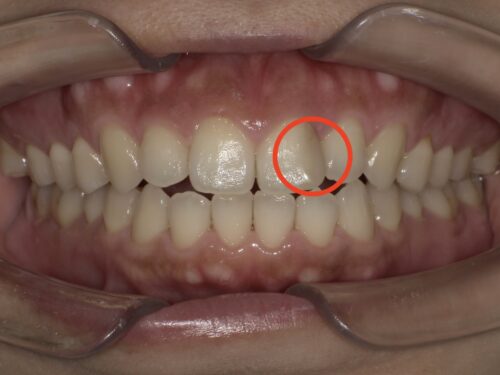

ただ、もう1箇所、この赤いマルで囲まれた部分をよーく見ていただくと、

ここに古い詰め物がついていて、変色しているのがわかります。

おそらく以前むし歯になって治療されたのだと思いますが、

コンポジットレジン(CR)という樹脂製の材料を使用されているようです。